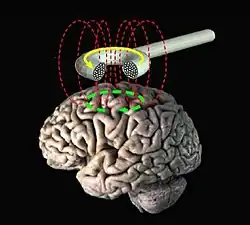

La estimulación magnética transcraneana se basa en el principio de inducción electromagnética descrito por Michael Faraday en 1838. Se aplica una corriente eléctrica de determinada fuerza y duración proveniente de una bobina de estimulación ubicada sobre el cuero cabelludo, lo cual genera campos magnéticos que penetran hasta el cerebro con una atenuación insignificante. Estos campos magnéticos inducen una corriente eléctrica en el tejido neural, cuyo volumen depende de la forma y tamaño de la bobina de estimulación, de la fuerza (intensidad) del campo magnético y de la frecuencia y la duración de los pulsos magnéticos producidos.[1]

La aplicación de la EMT requiere de un transductor que el operador ubica sobre el lugar que se quiere estimular. El operador puede controlar la posición del transductor, la focalización, la intensidad y la frecuencia del estímulo. En la estimulación de la corteza cerebral, la posición debe ser perpendicular al surco central del cerebro con un flujo diagonal de atrás hacia delante. La intensidad se ajusta regulando la corriente que fluye por el transductor, lo cual modifica la magnitud del campo magnético inducido y, por lo tanto, del campo eléctrico secundario inducido. El foco depende de la forma del transductor, ya sea en forma de ocho o circular. El primero permite una estimulación más focalizada, con lo que permite un mapeo más fino de la representación cortical. El segundo induce un campo eléctrico distribuido más ampliamente, y así permite la estimulación simultánea de ambos hemisferios, muy útil en estudios de tiempos de conducción. Por último, la frecuencia del estímulo puede ser modificada para lograr diferentes efectos sobre una región determinada del cerebro.[2][5]